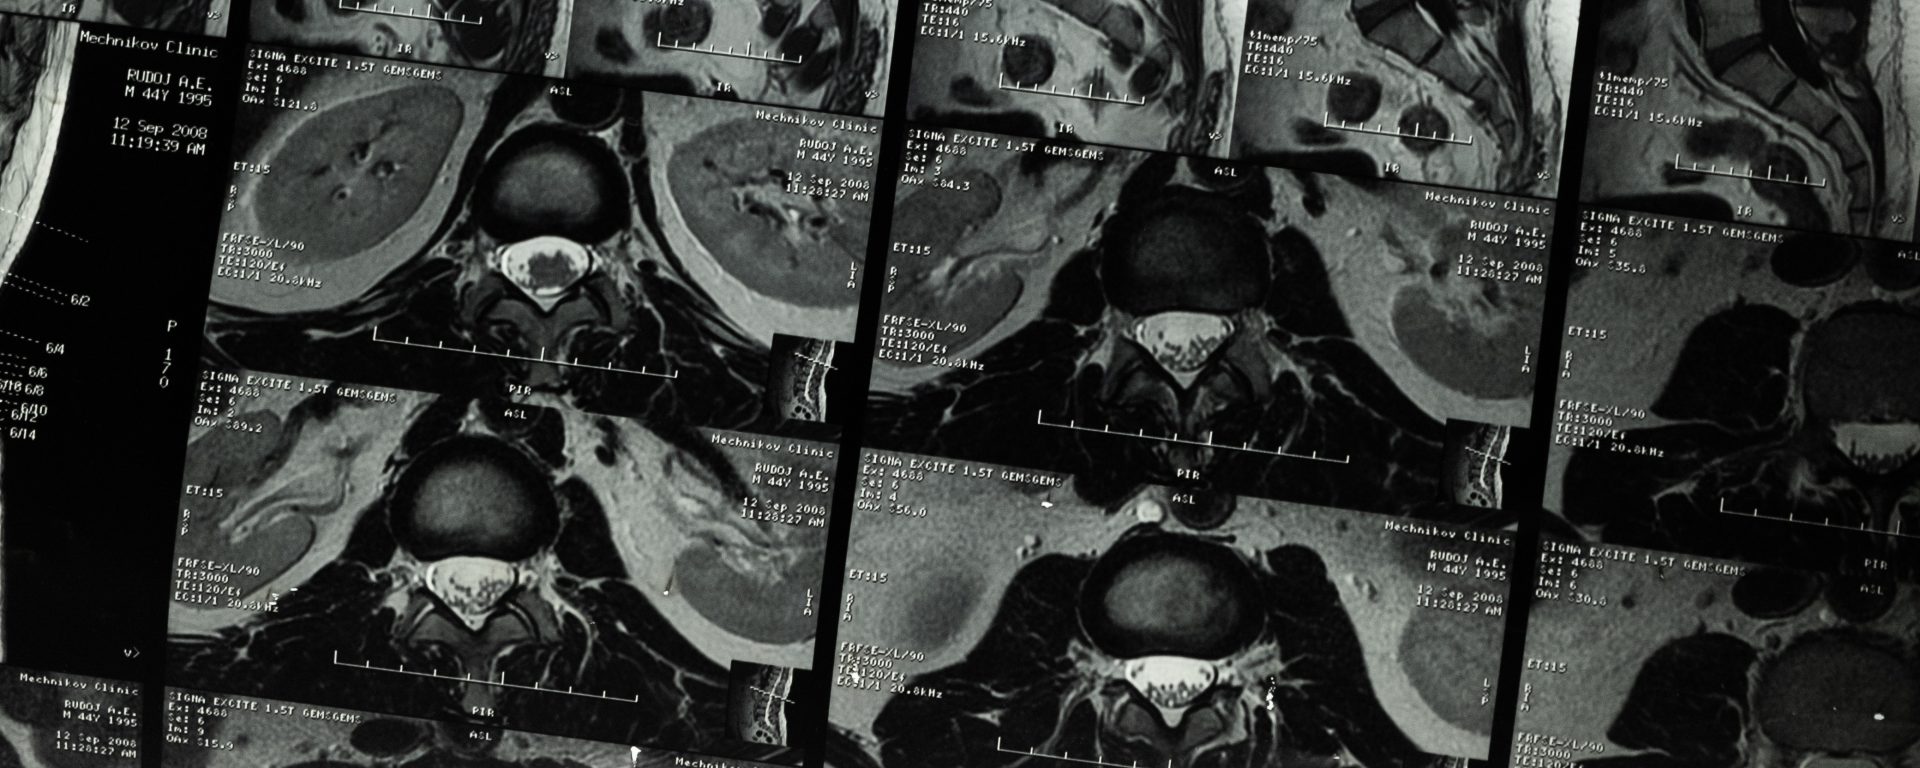

First, in the upper lumbar region, the root sleeve is located well below the disc level. An upper lumbar herniation impinging upon the dural sac will tend to displace rather than compress the upper lumber root, as the roots have more freedom of movement in the transverse plane (3).

Also, in the upper lumbar region, the oval shape of the canal and the dural sac without lateral recesses may be the reasons for lower rates of nerve root compression (3).

In the lower lumbar region, the axilla of the root sleeve is located much closer to the disc level. This is more common at the L5/S1 level, frequently even above this level. Therefore, a lower lumbar herniation is much more likely to compress the nerve root (3).

At L4/5 & L5/S1, where most disc herniations occur, the shape of the spinal canal is “triangular”. Therefore, there is a clearly defined lateral recess in the lower lumbar region (3). These lateral recesses tend to fix the root sleeve in place and prevent the nerve root from moving backward out of harm’s way when encroachment by a herniated disc takes place (3).